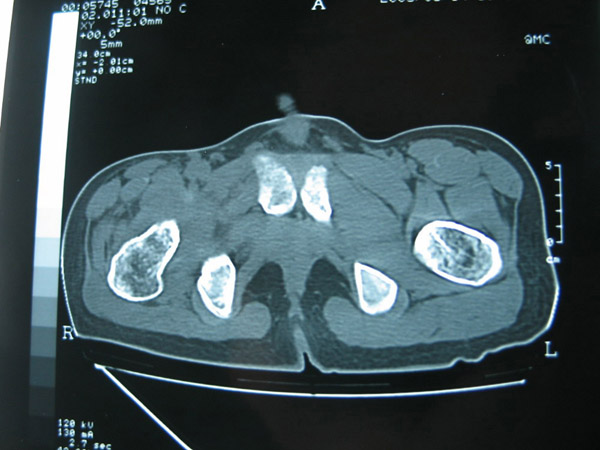

以下是引用hhcckk在2007-1-25 17:18:00的发言:[br][br]支持髋关节结核,[br]依据关节面破坏,有脓肿,脓腔内有钙化,关节周围增生不明显,鉴别[br]1化脓性的病变增生明显,临床上有高热[br]2创伤引起的关节炎,无菌坏死不会引起关节面的破坏,而且不会在这么短的时间内出现[br]

以下是引用卜一在2007-1-25 16:33:00的发言:[br]右侧髋关节股骨头及髋臼骨骨小梁疏松 粗糟,股骨头外形毛糟,软组织似肿胀,间隙略变窄.考虑:1 髋关节结核可能性大.2 缺血性坏死?3 化脓性髋关节炎?